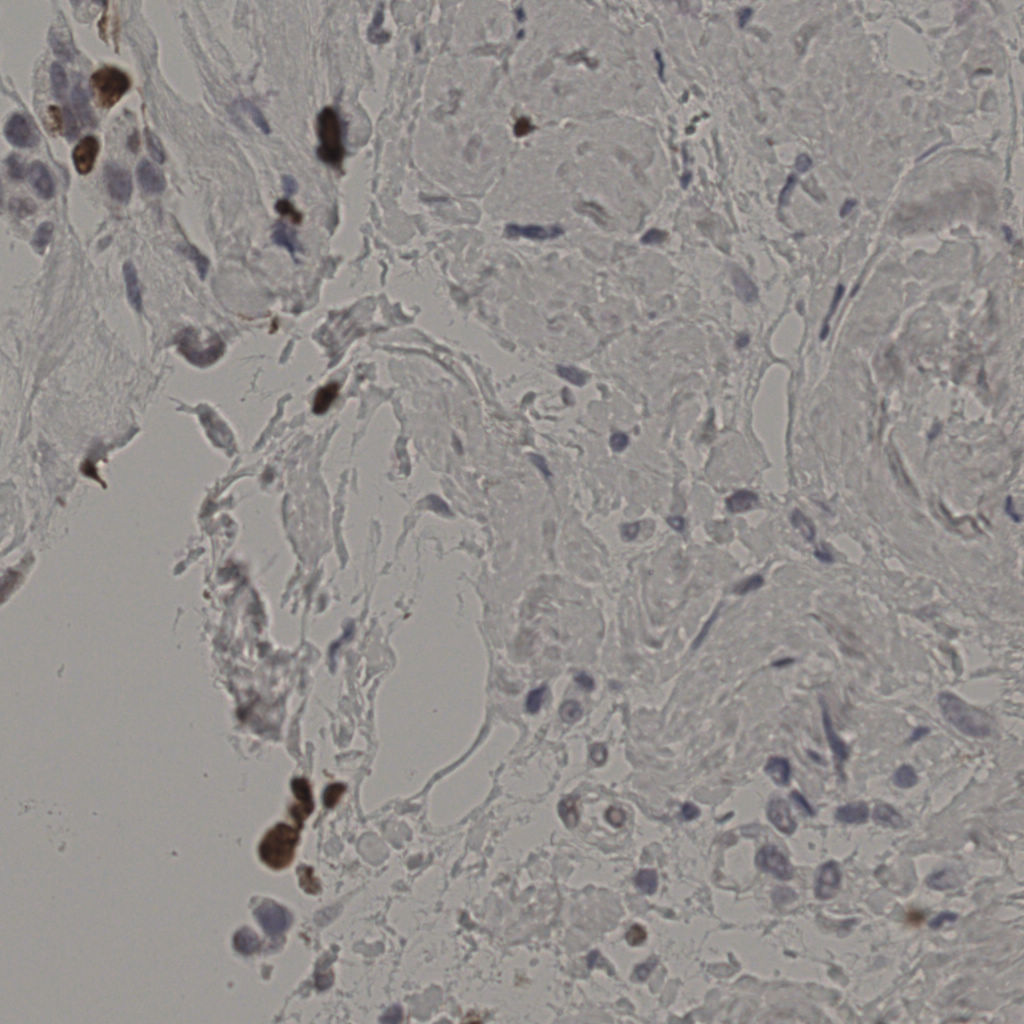

17.75%

Ki67 指数

阴 7986 阳 1723

切片统计

总切片 2640

有效 412

已标记 412

有效率 16%